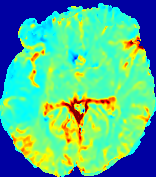

Figure 3: PIANO feature maps for one stroke patient, where the lesion is located in the left hemisphere. Top row: segmented stroke lesion region (white) on different slices, obtained from ISLES 2017. The corresponding slices for the PIANO feature maps are shown in the following rows.

For a better insight into an estimated velocity field 𝐕𝐕{\bf{V}} and diffusion field 𝐃𝐃{\bf{D}}, we compute the following maps: (1) 𝐕rgbsubscript𝐕𝑟𝑔𝑏{\bf{V}}_{rgb}: Color-coded orientation map of 𝐕=(Vx,Vy,Vz)T𝐕superscriptsuperscript𝑉𝑥superscript𝑉𝑦superscript𝑉𝑧𝑇{\bf{V}}=(V^{x},V^{y},V^{z})^{T}, obtained by normalizing 𝐕𝐕{\bf{V}} to unit length and mapping its 3 components to red, green, blue respectively; (2) 𝐕2subscriptnorm𝐕2\|{\bf{V}}\|_{2}: 222 norm of 𝐕𝐕{\bf{V}}; (3) D𝐷D: scalar field in Eq. 5.

Fig. 3 and Fig. 4 show the PIANO feature maps estimated from two ISLES 2017 patients: all are highly consistent with the lesion in both cases. Details of the blood flow trajectories are revealed in 𝐕rgbsubscript𝐕𝑟𝑔𝑏{\bf{V}}_{rgb} by the ridged patterns and the sharp changes of colors in the unaffected (right) hemisphere, while the flat patterns appearing within the lesion provide little directional information about the velocity and indicate low velocity magnitudes. Velocity magnitudes are more directly visualized via 𝐕2subscriptnorm𝐕2\|{\bf{V}}\|_{2}, from which one can easily locate the lesion where 𝐕2subscriptnorm𝐕2\|{\bf{V}}\|_{2} is low. D𝐷D also indicates lower diffusion values in the lesion, though with less contrast potentially due to the fact that it captures the accumulated effect of CA diffusion at the voxel-level.